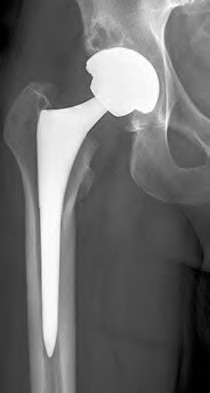

ORTHOPEDIC MCQS ONLINE RECON OB 20 1C 2020 A 72-year-old female presents with progressive left thigh and knee…

Orthopedic MCQS Reconstruction Adult Reconstructive Surgery of the Hip and Knee Scored and Recorded Self-Asse…